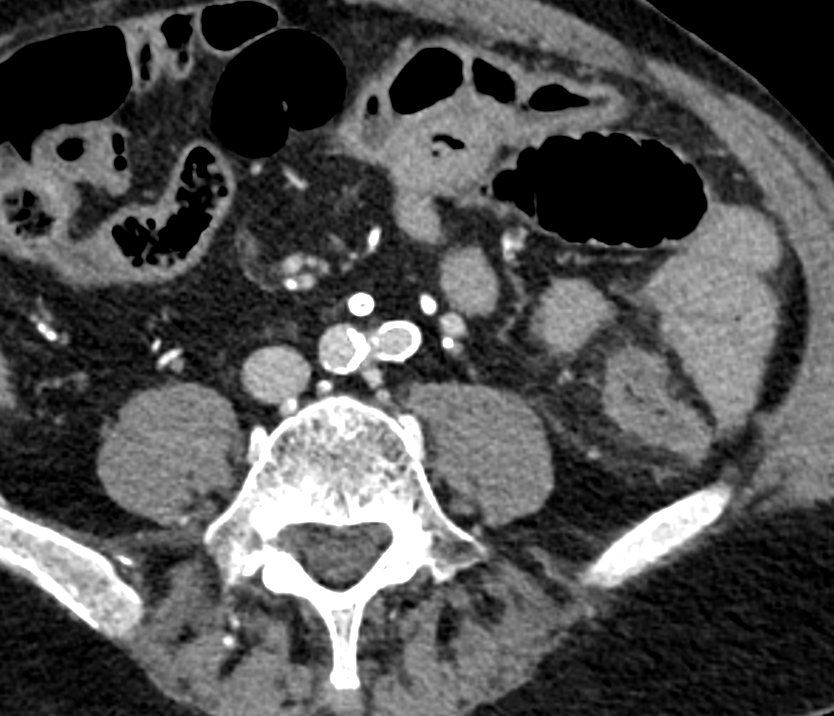

Infiltration du colon descendant jusqu’à la jonction sigmoidienne, patient avec de nombreuses calicifications vasculaires, défaut de rehaussement. Origine Hypovolémique

Infiltration du colon descendant jusqu’à la jonction sigmoidienne, patient avec de nombreuses calicifications vasculaires, défaut de rehaussement. Origine Hypovolémique